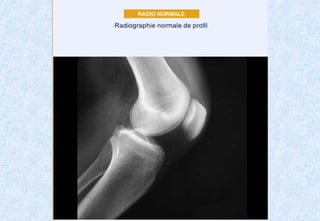

Radiographie d'un genou normal. L'espace entre fémur en haut et

tibia représente l'épaisseur du cartilage.

Radiographie d'un genounormal. L'espace entre fémur en haut et tibia représente l'épaisseur du cartilage.